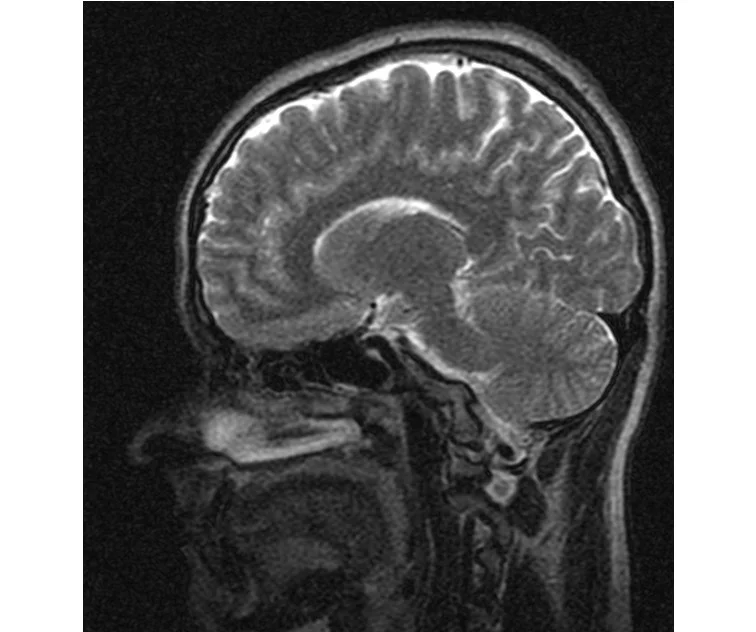

глянте на снимки томографии плиз

делал в обласной на siemense.В заключении выданом мне через 15мин.после мрт (легкая дегидрация)

Меня смутил факт выдачи заключения через 10мин(наверно они у них зарание напечатаные)я не медик.достаточно мимолётного взгляда на снимки?А вы видете на них гидроцефалию? Я лиш спросил куда идти с результатами томографии?и не хотел никого роздражать.

Я попросил взглянуть на снимки и сказать видна.ли на них гидроцефалия?или куда обратится за консультацией по этому вопросу?В мрт снимках наверно розбирается любой нервопатолог(я так предположил)

Я уже говорил, что независимо от того, есть на МРТ гидроцефалия или нет, лечиться тебе нужно только в том случае, если есть какие-либо проявления болезни, иначе на все эти анализы можешь забить... Но давай все-таки разберемся с томограммой.

Итак, с самого начала томограмма обозначала срез какого-либо органа на определенной глубине, позволяла заглянуть вовнутрь. При компьютерной томографии аппарат делает десятки срезов головного мозга в разных направлениях и из этого множества срезов он моделирует полноценное объемное изображение мозга в натуральную величину. Обрати внимание, компьютер работает не с этими миниатюрными изображениями, а с трехмерной моделью в масштабе 1:1. Эту модель вдоль и поперек анализирует суперсовременный компьютер, выполняющий миллионы операций в секунду. Только ***** может пытаться перепроверить компьютер, ведь человеку не хватит всей жизни чтобы проанализировать то, что компьютер с тобой сделал за 10 минут. Я хочу, чтобы ты это понял!

Ты разместл здесь несколько миниатюр и хочешь, чтобы врач по ним создал полноценное объемное изображение в натуральную величину, а потом осмотрел его со всех сторон и дал заключение? Но ведь это невозможно. Это просто насмешка над врачом, это издевательство над здравым смыслом. Принеси Букеру уменьшенный в 50 раз снимок зуба и спроси у него, в каком состоянии там корневые каналы. Или давай я дам тебе скрин со спутниковой карты города и попрошу тебя описать, какого цвета и какой модели запечатленная со спутника машина, какой у нее гос.номер, сколько в ней пассажиров, сколько из них мужчин и сколько женщин...